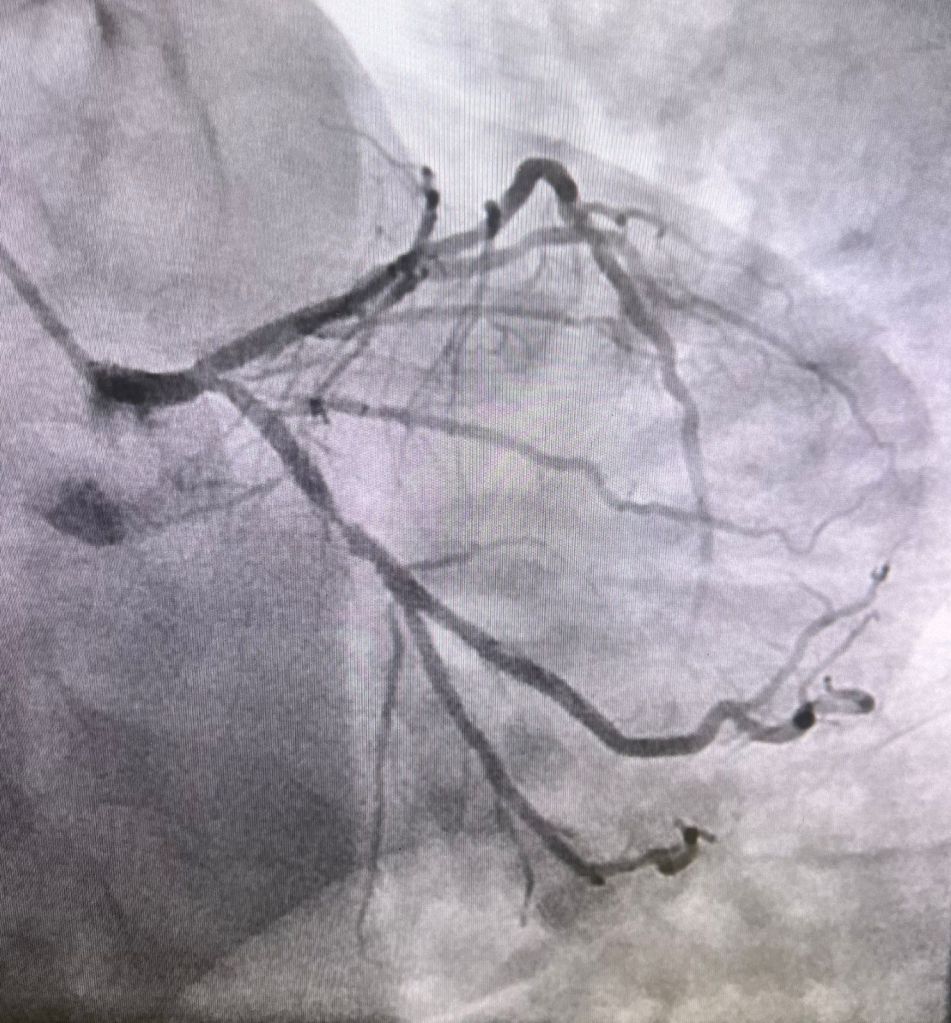

SE showed anterior and inf wall hk, Rest echo 65%ef, post exercise 45%.

LHC showed discrete lesions but diffuse 3 vessel disease, extensive but good targets. Scheduled for cabg next week.